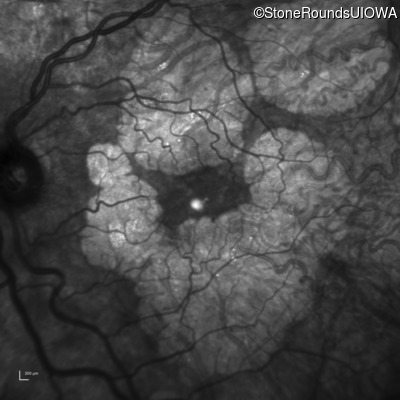

Infrared Fundus Photograph - Right - 20/20 -1

Exemplar

Infrared Fundus Photograph - Left - 20/20